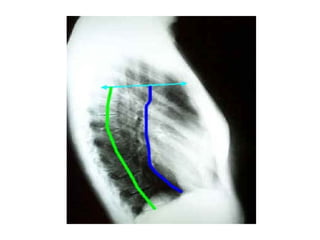

La  calcificación de la válvula aórtica está superpuesta a la columna en la proyección pa. por lo que no es visible. En la radiografía lateral puede verse a mitad de camino entre el borde cardiaco posterior y anterior. Si se traza una línea que, pasando por la bifurcación traqueal, llegue hasta el ángulo esternodiafragmático anterior, la válvula aórtica que­da por delante mientras que la válvula mitral queda por detrás.